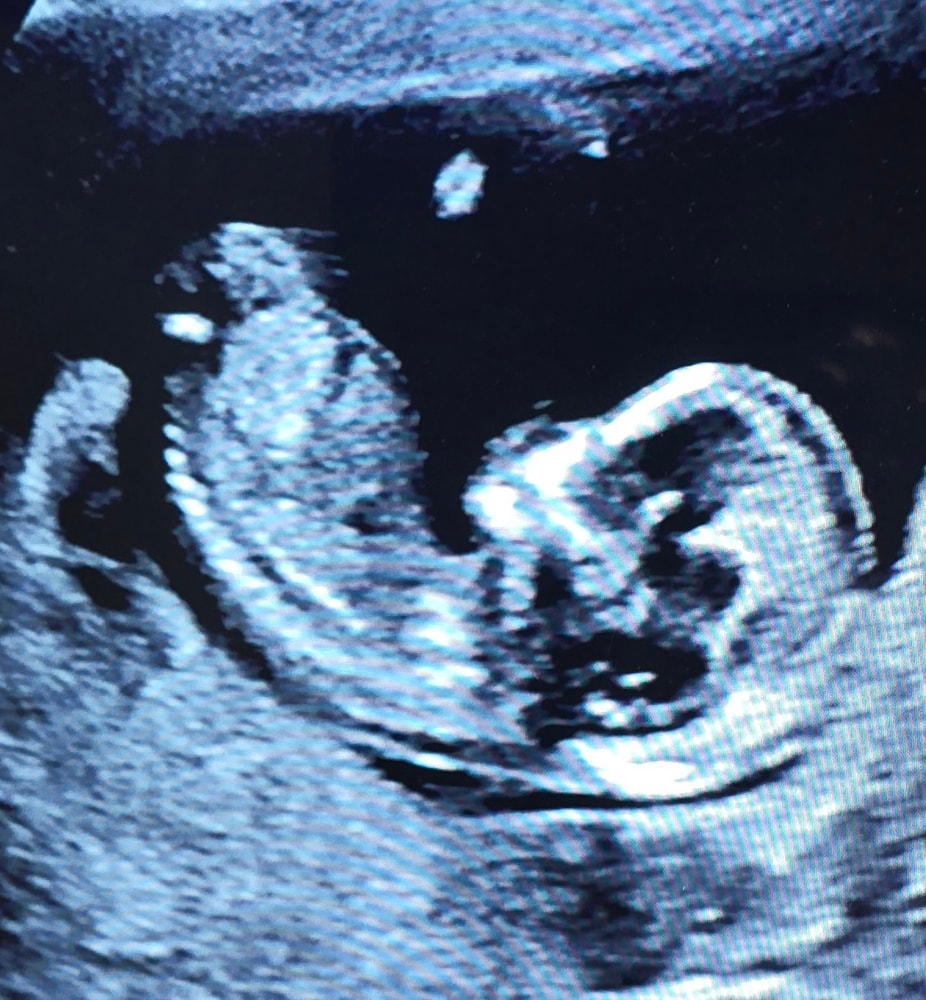

УЗИ, КТГ, доплерСегодня был первый скрининг, срок чуть больше, чем предполагали, 13,2 нед. Малыш раскинуть ножки решил, вот не пойму: это пирожок или бананчик???

Ладно. Пол в другой проекции смотрят, но интуиция моя подсказывает, что девочка у вас. То есть, предположу, что пирожок.

Я не разбираюсь где смотреть пестик или тычинку :), хочу другое сказать, у них таких маленьких и уже такие разные черты лица, вот же удивительно 🩷 Лапочка 🌼